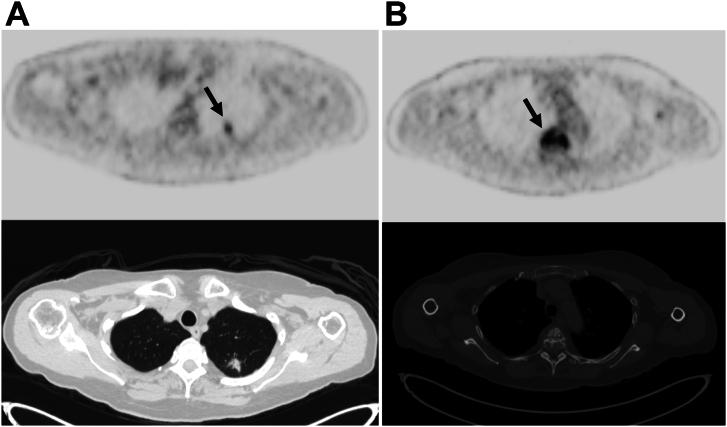

Vertebral hemangiomas (VHs) are common, benign angiomatous lesions of the spine with an incidence rate of 10% to 12% in the population. VHs have a characteristic appearance on imaging; however, a subset demonstrate atypical features that resemble more sinister pathologic processes, such as malignant neoplasms or metastatic disease. We report a case of an atypical VH that was initially thought to be a metastasis in a 75-year-old patient with a newly diagnosed pulmonary nodule. Our goal is to highlight the key findings of VHs on various imaging modalities that can potentially help minimize unnecessary investigations or interventions.

椎体血管瘤(VHs)是脊柱常见的良性血管瘤病变,在人群中的发病率为10%至12%。VHs在影像学上有特征性表现;然而,一部分显示出非典型特征,类似于更凶险的病理过程,如恶性肿瘤或转移性疾病。我们报告一例非典型VH病例,该病例最初被认为是一名75岁新诊断为肺结节患者的转移瘤。我们的目的是强调VHs在各种影像学检查中的关键表现,这可能有助于尽量减少不必要的检查或干预。